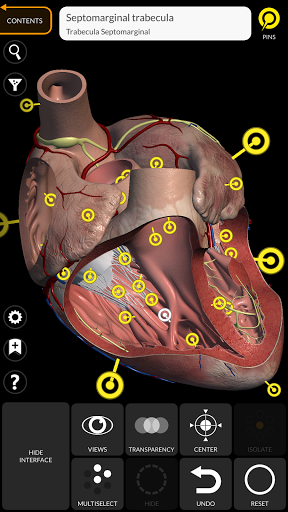

"Anatomy 3D Atlas" vous permet d'étudier l'anatomie humaine de manière simple et interactive.

Grâce à une interface simple et intuitive, il est possible d'observer chaque structure anatomique sous n'importe quel angle.

Les modèles anatomiques 3D sont particulièrement détaillés et avec des textures jusqu'à une résolution de 4k.

La subdivision par régions et les vues prédéfinies facilitent l'observation et l'étude de parties individuelles ou de groupes de systèmes et les relations entre différents organes.

• Système cardiovasculaire

• Option pour masquer ou isoler un ou plusieurs modèles sélectionnés

• En sélectionnant un modèle ou une épingle, le terme anatomique associé apparaît

• Description des muscles : origine, insertion, innervation et action